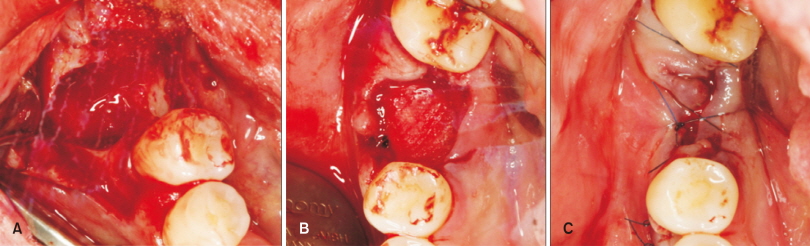

57세 남자 환자가 #46번 치아의 심한 치주염을 주소로 내원하였다. 방사선 사진에서 근단 부위를 넘어선 심한 골파괴와 함께 치조골의 골경화 양상을 관찰할 수 있었다(Fig. 1). 발치 후 자연 치유된다면 추후 치료가 어려워질 것을 예상하여 치조제 보존술을 계획하였다. 염증 조직의 확실한 제거를 위해 판막을 거상하였으며, 발치 후 협측과 근단측으로 연장된 염증성 육아 조직을 철저히 소파하였다. Tetracycline 용액을 cotton ball을 이용하여 발치와벽과 연조직 부위에 적용하였다. 10% 콜라겐이 함유된 탈단백 우골(Bio-Oss®Collagen 250 mg; Geistlich Pharma, Wolhusen, Switzerland)을 과도한 힘을 주지 않으면서 발치와에 적용하였으며 흡수성 콜라겐 차단막(Bio-Gide®; Geistlich Pharma)을 두 겹으로 하여 이식된 탈단백 우골이 완전히 덮이도록 하였다. 판막이 최대한 접합되도록 봉합하였지만, 일차 봉합을 시도하지는 않았다(Fig. 2).

Fig. 2. Ridge preservation procedure. (A) After extraction, huge defect was observed. (B) Bovine bone mineral incorporated with 10% collagen was gently inserted. (C) Flap approximation was attempted without primary flap closure.